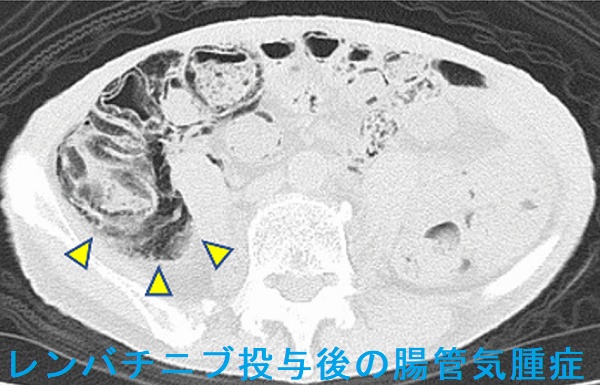

腸管気腫症(pneumatosis intestinalis)とは、大腸壁や小腸壁の粘膜下層・漿膜下層にガスが溜まり、気腫(空気嚢胞)を形成する病態。原因として、約15%は特発性ですが、約85%は続発性で、

- ステロイド薬・免疫抑制剤;腸管壁萎縮や免疫力低下によるガス産生菌増殖

分子標的薬(チロシンキナーゼ阻害薬) ベバシズマブ(アバスチン®)[甲状腺機能低下症も併発]、スニチニブ、レンバチニブ[J Med Case Rep. 2021 Nov 12;15(1):556.]、ダブラフェニブ・トラメチニブ[J Med Case Rep. 2021 Mar 2;15(1):109.];腸壁への血流障害

- 重度の便秘(甲状腺機能低下症);腸管内圧の上昇

腸管気腫症は、無症状で自然軽快することが多い。腹痛・血便を伴う場合は絶食や酸素投与、手術切除。

甲状腺乳頭癌肺・骨転移に対するダブラフェニブ・トラメチニブ投与後4カ月で見つかった腸管気腫症[J Med Case Rep. 2021 Mar 2;15(1):109.]